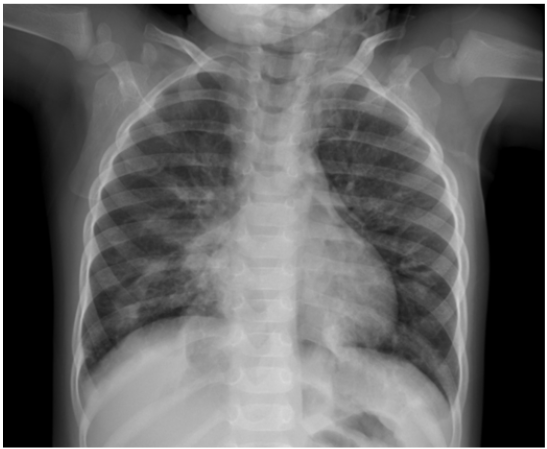

This report presents the case of a one year six months old female infant who was born in Belgium without a family history of importance for the condition reported below. The patient resulted from a normally progressing pregnancy with proper prenatal care. She was born at 36.4 weeks of gestation by childbirth without complications, with adequate weight and height, without requiring advanced resuscitation maneuvers. The patient had a complete vaccination scheme for her age, according to her country of origin, and had no personal pathological history of importance. The reported condition started in December 2019, 2 days prior to her admission to the urgent care, during air travel from Belgium to Mexico. The picture was characterized by asthenia, adynamia and irritability, an increase in temperature to 37.5°C; watery rhinorrhea; irritative and productive cough with coughing spells of 3-5 spells, with long intervals, non-cyanotic, non-dyspneic nor emetic, and with no predominance of schedule. The patient was taken to a private pediatric hospital due to initial symptoms of tachypnea, the temperature of 38.8°C, recurrent every 6 hours, and the following vital signs: respiratory rate of 70 breaths per minute, heart rate of 184 beats per minute, blood pressure of 102/48 mmHg, the temperature of 38.4°C, ambient air saturation of 72%, irritability that was comforted by parents, data of severe shortness of breath at the expense of suprasternal retraction, intercostal retraction, and thoracoabdominal dissociation. The thorax presented prolonged expiration and dispersed crepitant rales, with hypoventilation areas, and the rest of the exploration without other alterations (Figure 1).

Figure 1: First radiography in PA projection (a) and lateral projection (b).

a) We can see an increase in the thickness and radiopacity at the both perihilar region, in addition to identifying an incipient

consolidation area in the medial segment of the middle lobe.

b) There are atelectasis bands in the middle lobe topography in addition to perihilar filling.